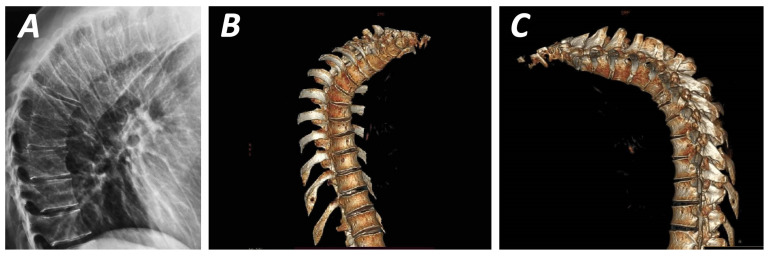

La malattia di Scheuermann

La malattia di Scheuermann (cifosi giovanile) rappresenta una delle principali fonti di errore diagnostico, specialmente nei pazienti anziani in cui i segni radiografici dell’infanzia si sovrappongono ad una potenziale osteoporosi senile.11 Essa si caratterizza per la presenza di:

- cuneizzazione anteriore di tre o più vertebre toraciche contigue;

- presenza di nodi di Schmorl (erniazioni del disco nelle piastre terminali);

- irregolarità diffuse delle limitanti somatiche e restringimento dello spazio discale.

La distinzione è cruciale perché la malattia di Scheuermann non è legata alla densità ossea e non richiede, di per sé, un trattamento con farmaci anti-riassorbitivi come i bisfosfonati. Un paziente può avere una BMD normale o addirittura alta e presentare molteplici vertebre cuneizzate a causa di un pregresso Scheuermann; interpretare questi dati come fratture osteoporotiche porterebbe a un sovratrattamento farmacologico inutile e potenzialmente dannoso.